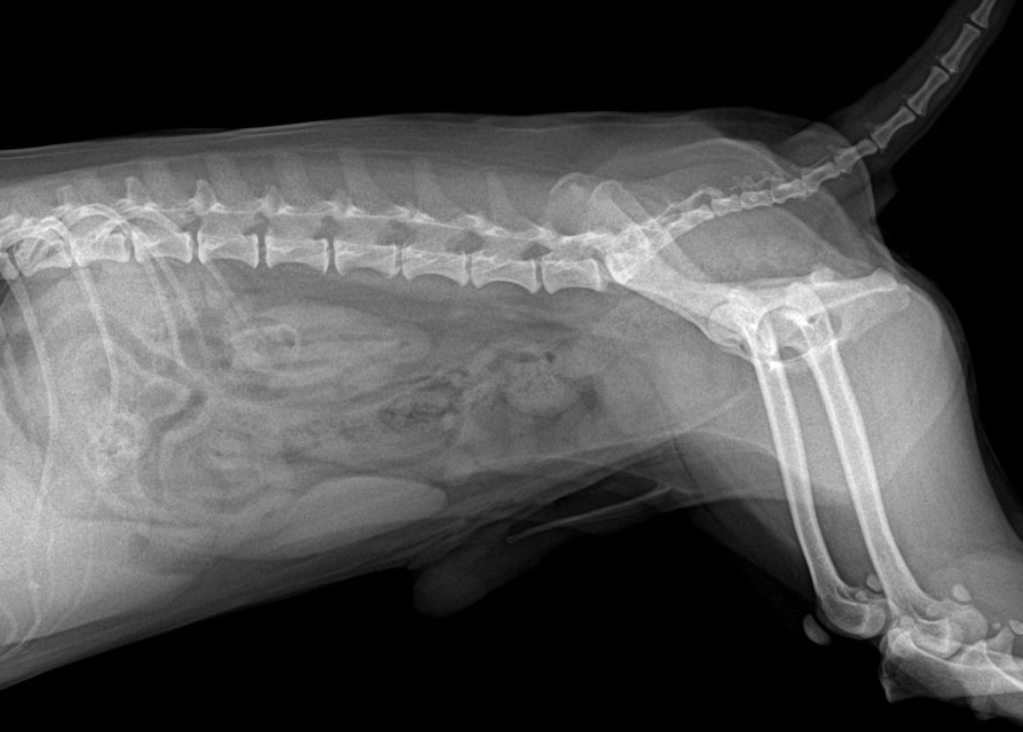

3️⃣ 방사선 검사(X-ray) 결석의 위치와 크기를 확인하는 기본 검사입니다.

대부분의 결석은 방사선에서 확인되지만, 종류에 따라 잘 보이지 않는 경우도 있습니다.

4️⃣ 초음파 검사

방광벽 두께, 염증 상태, 작은 결석 여부까지 확인할 수 있습니다.

요도 방향 이동 가능성도 함께 평가합니다.